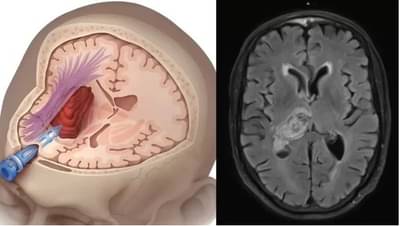

मेंदूच्या नसांमध्ये रक्तप्रवाह करणाऱ्या नसांना दुखापत झाली किंवा त्या फुटल्या तर आपल्याला पक्षाघात किंवा ब्रेन स्ट्रोक येत असतो. त्यामुळे शरीराचे अवयव लुळे होऊ शकतात. किंवा दृष्टी, बोलणे वा चालणे अथवा ऐकणे अशा क्रियांवर परिणाम होऊन त्या बंद देखील पडू शकतात. किंवा मेंदूत अधिक रक्तस्राव झाला तर मृत्यू देखील येऊ शकतो..

जेव्हा मेंदूची एखादी नस ब्लॉक होते तेव्हा ब्रेन स्ट्रोक येतो. या जीवघेण्या स्थिती वेळीच उपचार न केल्यास मृत्यू देखील येऊ शकतो.परंतू तुम्हाला मिनी ब्रेन स्ट्रोक बद्दल माहिती आहे का? जो एखाद्या मोठ्या अटॅक येण्याआधीच येऊ शकतो.याची लक्षणं हलकी असतात. त्यांना वेळीच ओळखले तर मोठा अटॅक येण्यापासून वाचता येते. याला मिनी ब्रेन स्ट्रोक वा ट्रान्सिएंट इस्केमिक अटॅक देखील म्हणतात

ब्रेन स्ट्रोक ज्याला पक्षाघात देखील म्हणतात. या आजाराचे संकेत शरीर काही तास आधी देत असते. एक दिवस आधी आपल्या संकेत मिळतात. त्यामुळे ब्रेन स्ट्रोकचा मोठा झटका येण्याआधी उपचार सुरु केल्यास रुग्णाला वाचवता येते.